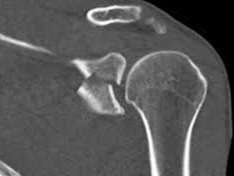

어깨에 골절이 발생하면 일상 전체가 마비되는 기분을 느끼는 것도 무리는 아닙니다. 특히 쇄골, 상완골 근위부, 견갑골 부위에 골절이 생기면 수술이 필요하며, 수술 이후의 재활과 물리치료는 단순히 통증을 없애는 것을 넘어, 관절 가동 범위의 회복과 장기적인 기능 정상화를 위한 핵심 단계입니다. 또한 어깨 골절 수술 이후 본격적으로 시작되는 재활 치료와 도수치료의 현실적인 문제는 ‘비용’과 ‘보험 적용 여부’입니다.